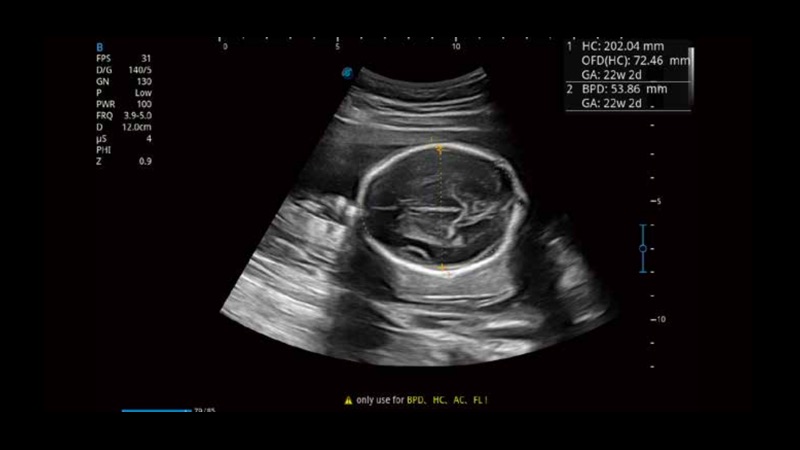

S-Fetus基于大數(shù)據(jù)深度學(xué)習(xí)算法,能夠幫助您在產(chǎn)前篩查過程中智能識(shí)別胎兒標(biāo)準(zhǔn)切面、自動(dòng)測(cè)量并錄入報(bào)告。一個(gè)按鍵,即可智能、精準(zhǔn)、高效地獲取胎兒生理指標(biāo),極大簡化您的產(chǎn)科檢查操作。

可快速對(duì)產(chǎn)科掃查切面完成胎兒生理學(xué)參數(shù)的自動(dòng)測(cè)量,減少操作者按鍵次數(shù),大幅提升檢查效率。